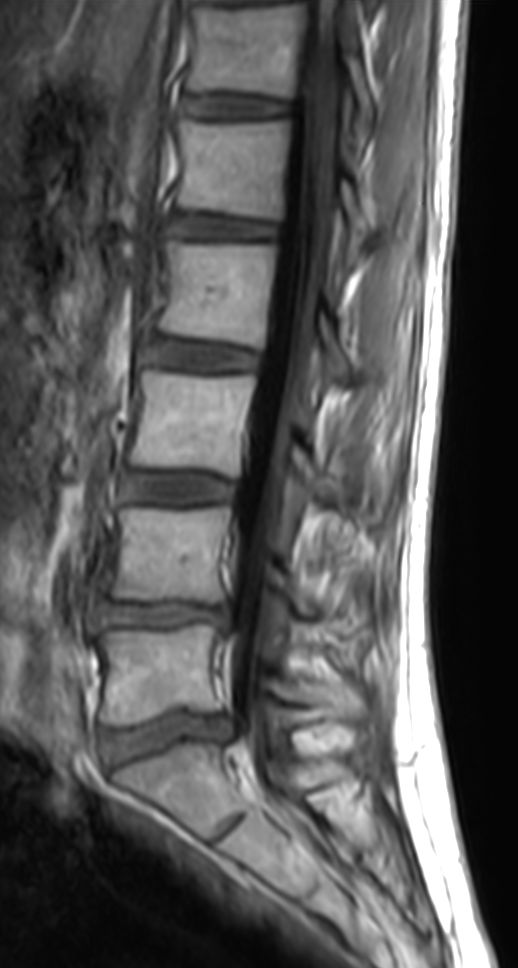

Sagittal T2w TSE

Sagittal PDw TSE

Sagittal T1w FLAIR